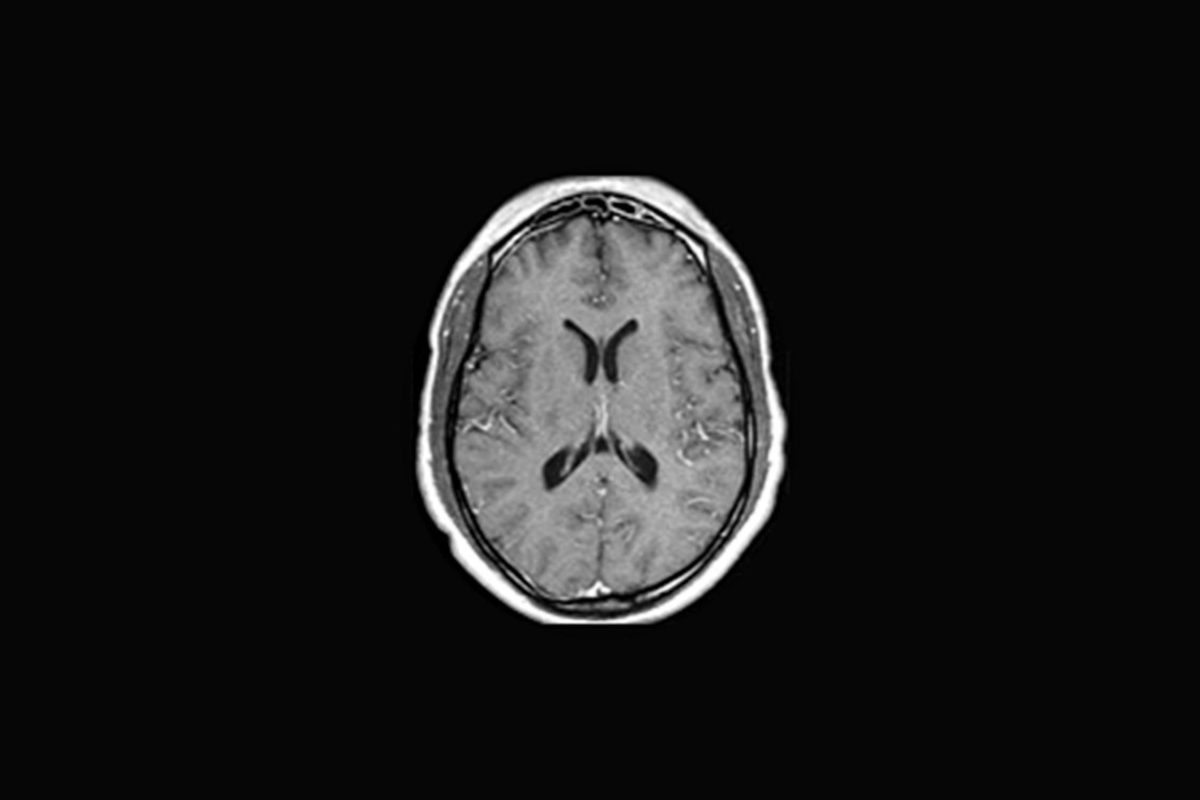

from farwestimaging.com